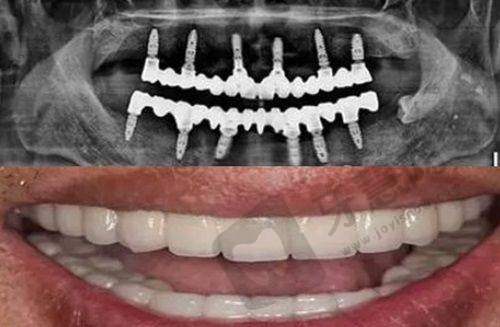

常见的治疗方法包括牙齿修复、正畸治疗、咬合板治疗等。牙齿修复可以通过补牙、镶牙等方式,修复牙齿的形态和功能;正畸治疗则是通过佩戴矫正器,调整牙齿的位置和排列;咬合板治疗是通过佩戴特殊的咬合板,来调整咬合关系,缓解咀嚼肌的紧张。这些治疗方法相互配合,共同实现咬合重建的目标。

咬合重建的治疗过程通常是一个较为复杂和漫长的过程。首先是诊断阶段,医生会对患者进行详细的口腔检查,包括口腔X光片、模型分析等,以确定患者的咬合问题和治疗方案。在这个阶段,患者需要积极配合医生,如实告知自己的症状和病史。